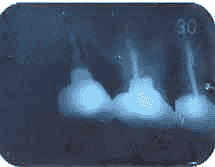

1.X線所見で根の先に黒いカゲが

見えます。これは歯の先に膿の

袋があり、まわりの骨をとかして

いる状態です。